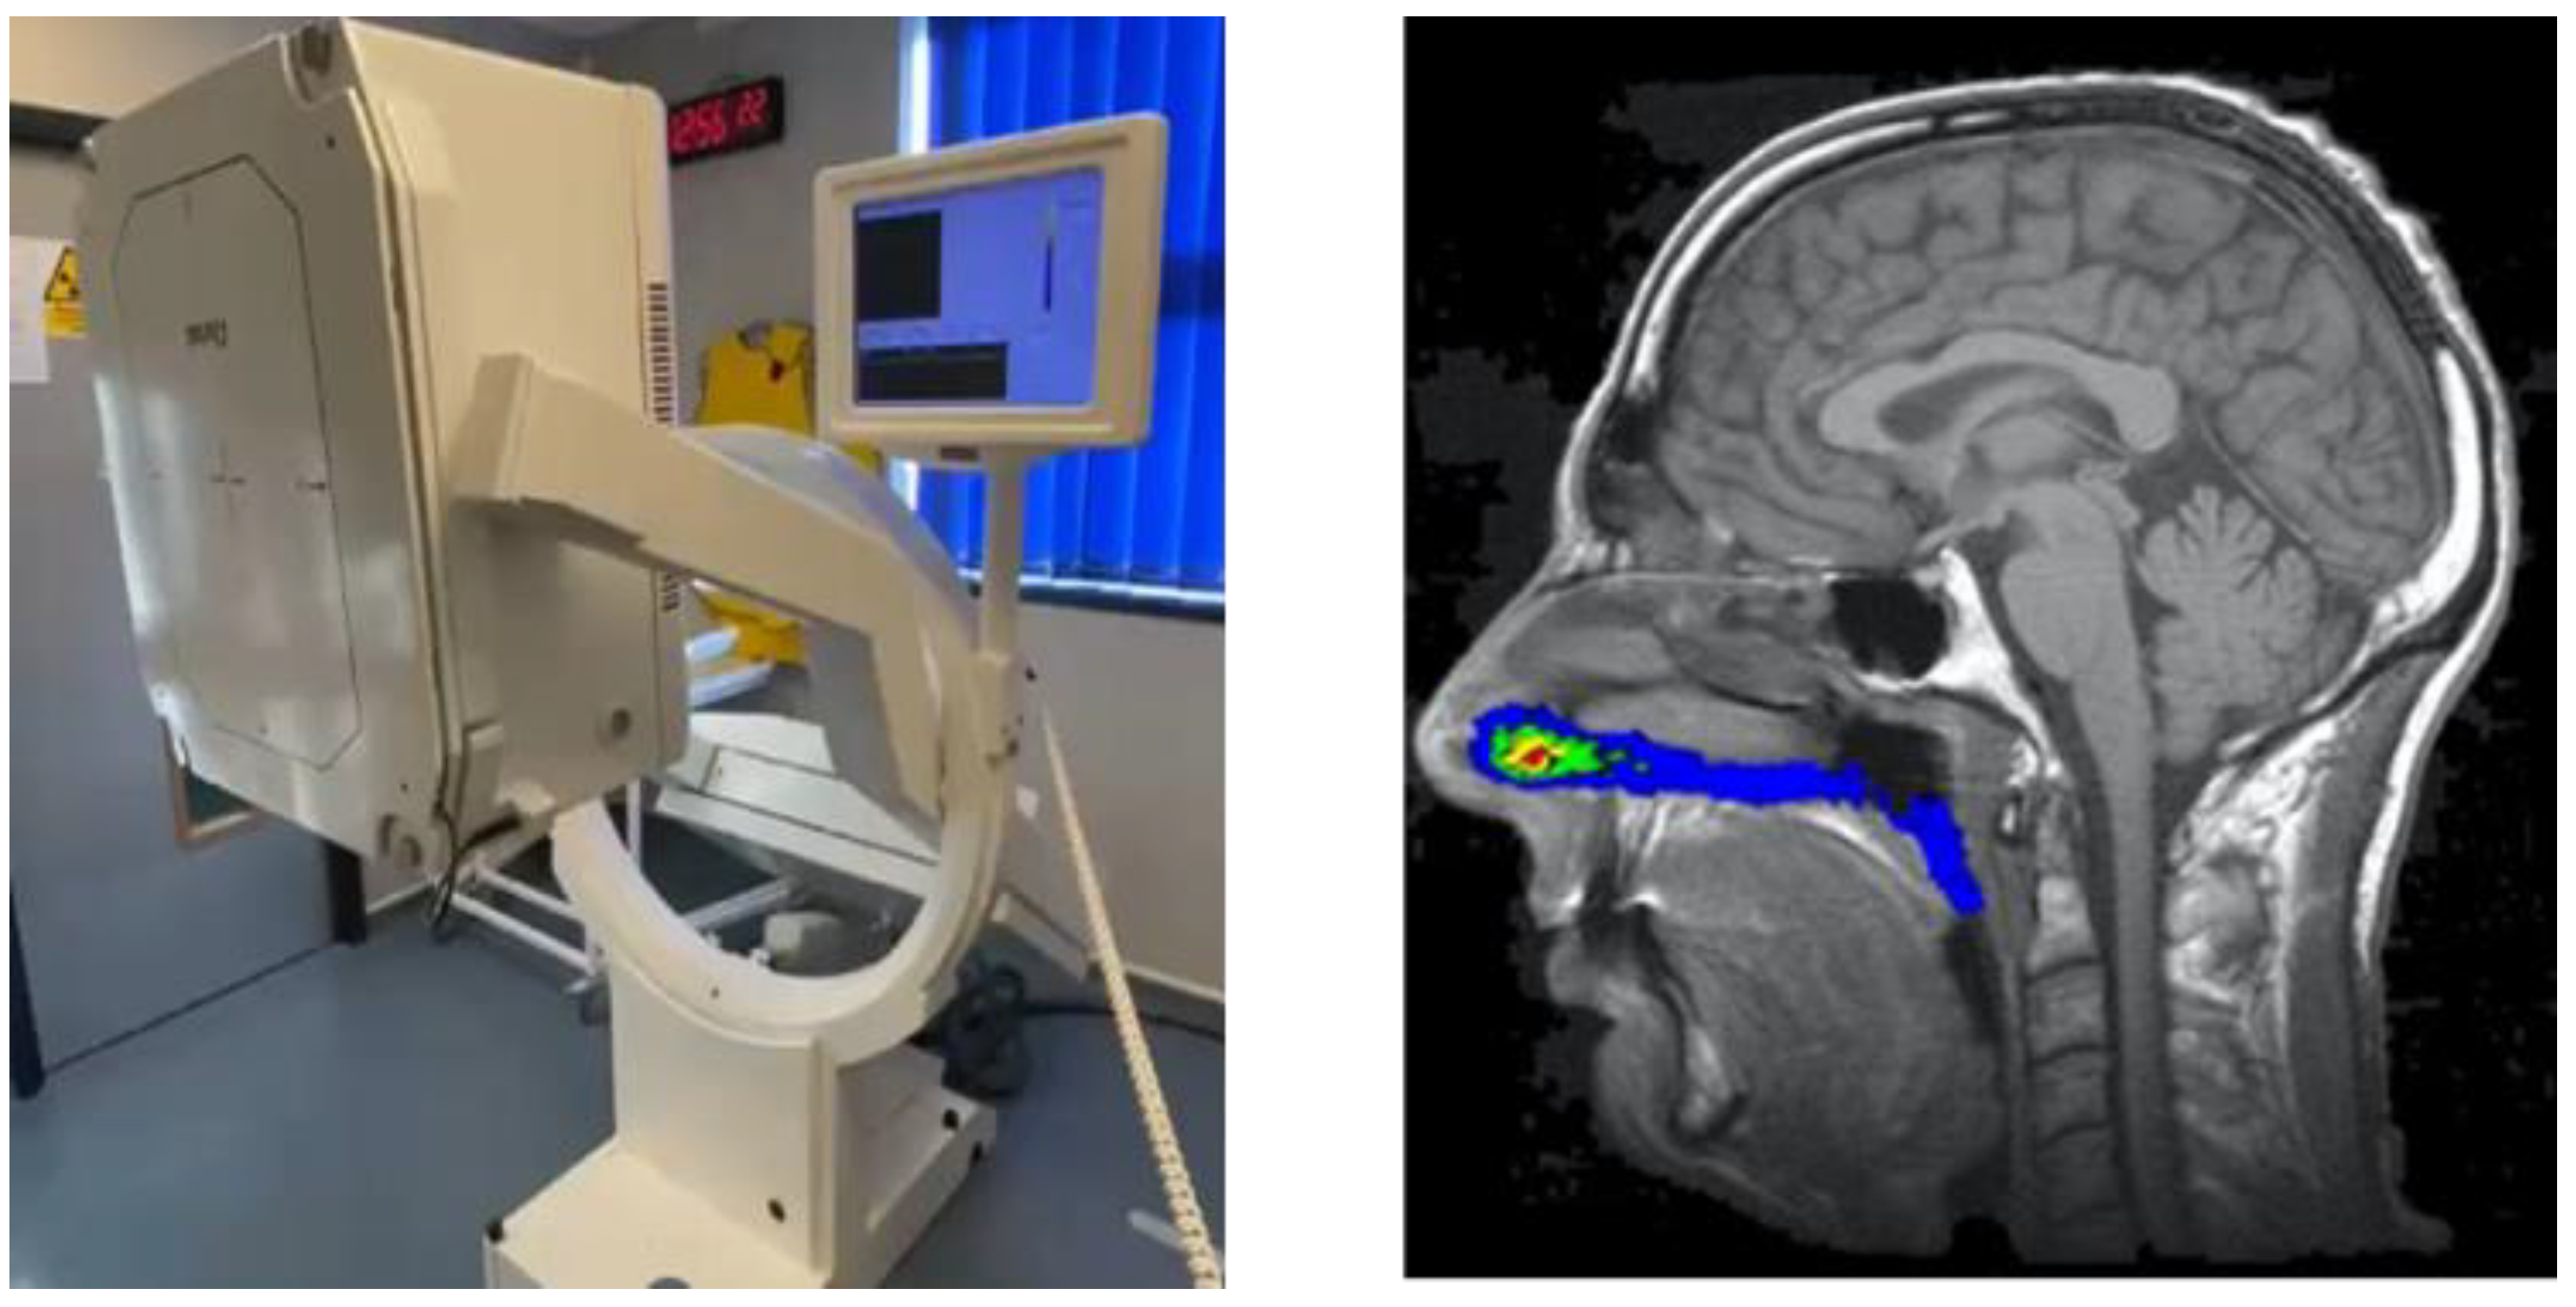

Two-dimensional, non-invasive gamma scintigraphy remains the most widely used imaging methodology to assess in vivo nasal drug delivery, although three-dimensional alternatives such as single-photon emission computed tomography (SPECT) and positron emission tomography (PET) are available [109]. Clinical studies using gamma scintigraphy allow for the quantification of deposition and clearance of formulations that have gamma-emitting radionuclides incorporated, typically technetium-99m (99mTc, radioactive decay half-life of 6 h), and visualized through image acquisition with a gamma camera. For nasal imaging studies, an individual’s nasal cavity shape and regions are defined through magnetic resonance imaging (MRI) with the images from the gamma camera being subsequently aligned with the MRI images on an individual specific basis (Figure 5).

Figure 5.

Gamma camera used to capture scintigraphic images (left) and composite (co-registered) MRI scan and nasal gamma scintigraphic image (right, colored areas represent scintigraphic radiation count intensity). Images from Quotient Sciences.

Deposition over time in the nasal cavity as a whole and/or regionally can then be quantified along with the amount of radiation being swallowed via the nasopharynx and reaching the lungs. In addition, images can capture the material remaining within the delivery device and any nasal wipes taken. Clinical studies using gamma scintigraphy in conjunction with MRI allow for key nasal delivery questions to be addressed, such as “how much is delivered?”, “what is the spread of deposition?”, “how long does it reside?” and “how much reaches the lungs?”. Where oral deposition or absorption is minimal following nasal administration, imaging data can also be considered in conjunction with any PK (blood, plasma and/or cerebrospinal fluid related) and biomarker data obtained from the same study subjects to provide greater insight into product performance. Importantly, the 99mTc radiolabel is not chemically bound to the drug in these studies; instead, it acts as a surrogate marker within the product formulation and is chelated to diethylenetriaminepentaacetic acid (DTPA). The 99mTc-DTPA complex itself is only absorbed by the nasal mucosa in minute quantities [110]. This radiolabel can be spiked into solution formulations and suspension vehicles for use in nasal devices including droppers, pump sprays, pressurized metered-dose inhalers (pMDIs), nebulizers and soft mist inhalers. Impactor, impinger or nasal cast methods [111] can be used to confirm that the process of radiolabeling itself does not affect product performance and that the surrogate marker is relevant, with pre- and post-labeling products tested and compared through both drug and radiolabel analyses of the fine particle fraction (FPF) % as a marker of the nasal product performance (Figure 6).